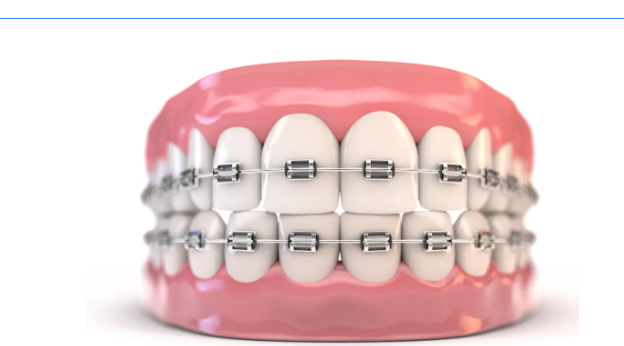

也叫普通金属托槽牙齿矫正器,是目前市面上最常见的矫正方法,采用金属托槽矫治,性价比高。这款矫治器适用于大部分的牙齿排列不齐、地包天和龅牙等问题,而且效果也很稳定。

它所使用的托槽材料均为氧化铝陶瓷,呈乳白色半透明或完全透明,与牙齿色泽一致,戴在牙齿上不易被发现,粘在牙齿上隐蔽性较好,使矫治过程悄然完成,而且对于金属过敏的人群是一个不错的选择。

隐形矫正技术由弹性透明的高分子材料制成,不需要托槽和钢丝,打破了传统矫正给人们所带来的“钢牙”形象,同时方便摘戴,不妨碍患者的日常生活。针对牙齿稀疏的问题,不仅矫正效果好,而且能让患者在不知不觉中完成矫治的过程,丝毫不用担心生活和工作会受到影响。